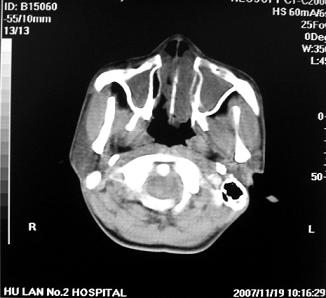

鼻窦炎伴息肉形成可能,上颌窦内侧壁明显骨质破坏并无挤压,膨胀改变,多不考虑内翻性乳头状瘤.

骨板增生增厚,支持考虑炎症伴息肉,不排除肉翻乳头状瘤

双侧鼻腔内低密度软组织影,骨壁无明显破坏,鼻腔无扩大,双侧上颌窦、筛窦软组织影,窦壁增厚,结合临床考虑鼻息肉合并慢性上颌窦炎。